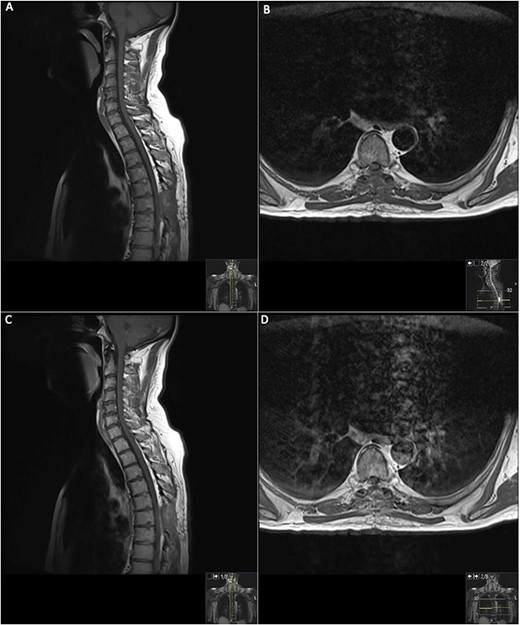

19 days post operative MRI; T1 pre-contrast sagittal (A) and T1 pre-contrast axial (B) show evidence of surgery at T6. Post-contrast T1 sagittal (C) and axial (D) show evidence of a small ‘fleck’ of dural enhancement, however, provide no evidence of any definite residual lesion.